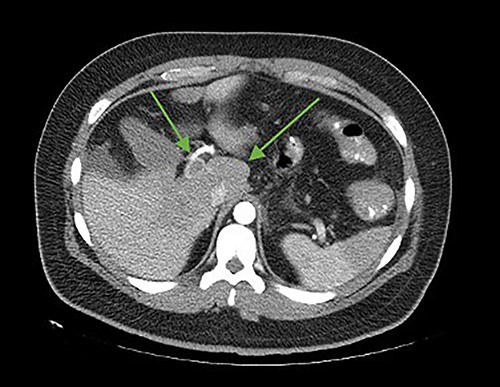

On the seventh postoperative day, he began with abdominal pain, tachycardia, fatigue, and anorexia, limited fluid intake and minimal ambulation. On the eighth day, the patient presented to the emergency department due to intolerance to oral feeding, acute abdominal pain (VAS 8/10), in antalgic position, tachycardic and diaphoretic. Physical examination revealed abdominal hyperalgesia and hyperalgesia. Laboratory tests revealed hemoglobin of 11 g/dl, 18 700 leukocytes (95.3% neutrophils), C-reactive protein of 13.3 mg/dl. Blood gases with pH 7.42, lactate 1.6 mmol/L. A contrast-enhanced abdominopelvic tomography showed portal, mesenteric, and splenic vein thrombosis associated with jejunal wall thickening with adjacent mesenteric changes and free fluid in the cavity (Figs 1 and 2).

Axial cut. In the arrows, there is a lack of splenomesenteric opacification towards the posterior part of the pancreas and striation of the adjacent peripancreatic fat. Edematous intestinal walls in the jejunum, free fluid in the left paracolic gutter.